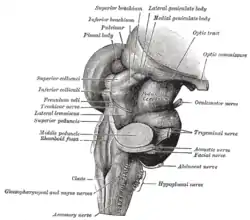

Hind- and mid-brains; postero-lateral view. | |